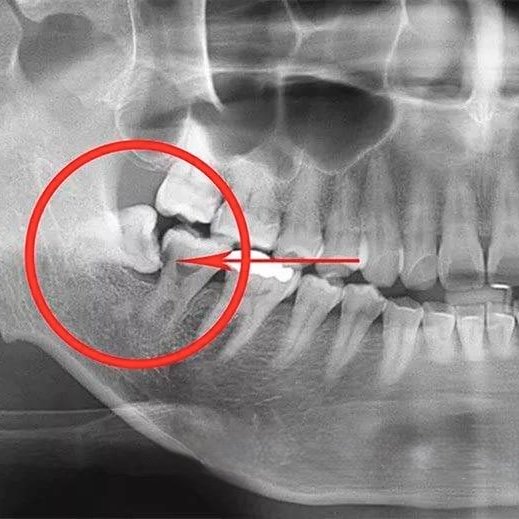

- ▪ Дистопія — це неправильне розташування зуба. Він може бути під нахилом, горизонтально або повернутий. Це тисне на сусідні зуби, викликаючи їх зміщення або руйнування. Такий тиск може спричинити біль, руйнування коренів сьомих зубів, а також збільшує ризик розвитку карієсу між зубами, до яких важко дістатися.

Стоматолог проводить огляд та призначає рентген-знімок (або КТ), щоб точно визначити розташування зуба, його коренів та сусідніх структур.